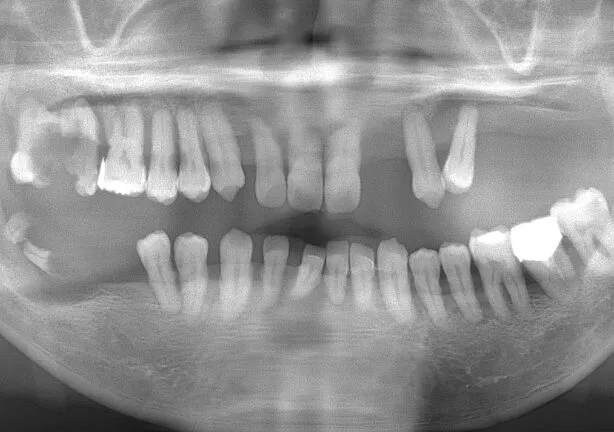

case1

Before